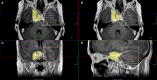

Background: The efficacy and safety of radiosurgery led to paradigm shift in the management of cavernous sinus meningiomas. Nevertheless, patients are still significantly affected by cranial nerve deficits related to the mass effect of these tumors. Our management strategy involves the combination of a functional surgical decompression followed by radiation therapy. Methods: We reviewed a single institution's cohort of patients who underwent endoscopic endonasal decompression (EED) for symptomatic meningiomas primarily involving the cavernous sinus (CS) from 2010 to 2016. The preoperative neuro-ophthalmological exam was compared to the 1- and 6-month postoperative exams. The patient's length of hospital stay, complications, and radiological and clinical follow-up were noted. Results: A total of 17 patients underwent EED for CS meningiomas that fit our radiological criteria. The final outcome at the 6-month visit showed five patients (62.5%) with normalization of deficit and three patients (37.5%) with partial improvement of the CNII deficit. Out of the 12 patients who had cavernous sinus cranial nerves (CSCN) deficits, the final outcome at the 6-month visit showed four patients (33.33%) with normalization of deficit, seven patients (58.3%) with partial improvement, and one patient (8.33%) with no improvement. There were no intraoperative complications. Conclusion: The EED for CS meningiomas is a valuable technique when addressing acute/subacute CNII and CSCN deficits. This conservative surgical approach showed good functional outcomes, low morbidity, and low complication rates. However, it does not exempt the need for radiosurgery/radiation therapy for control of tumor growth.